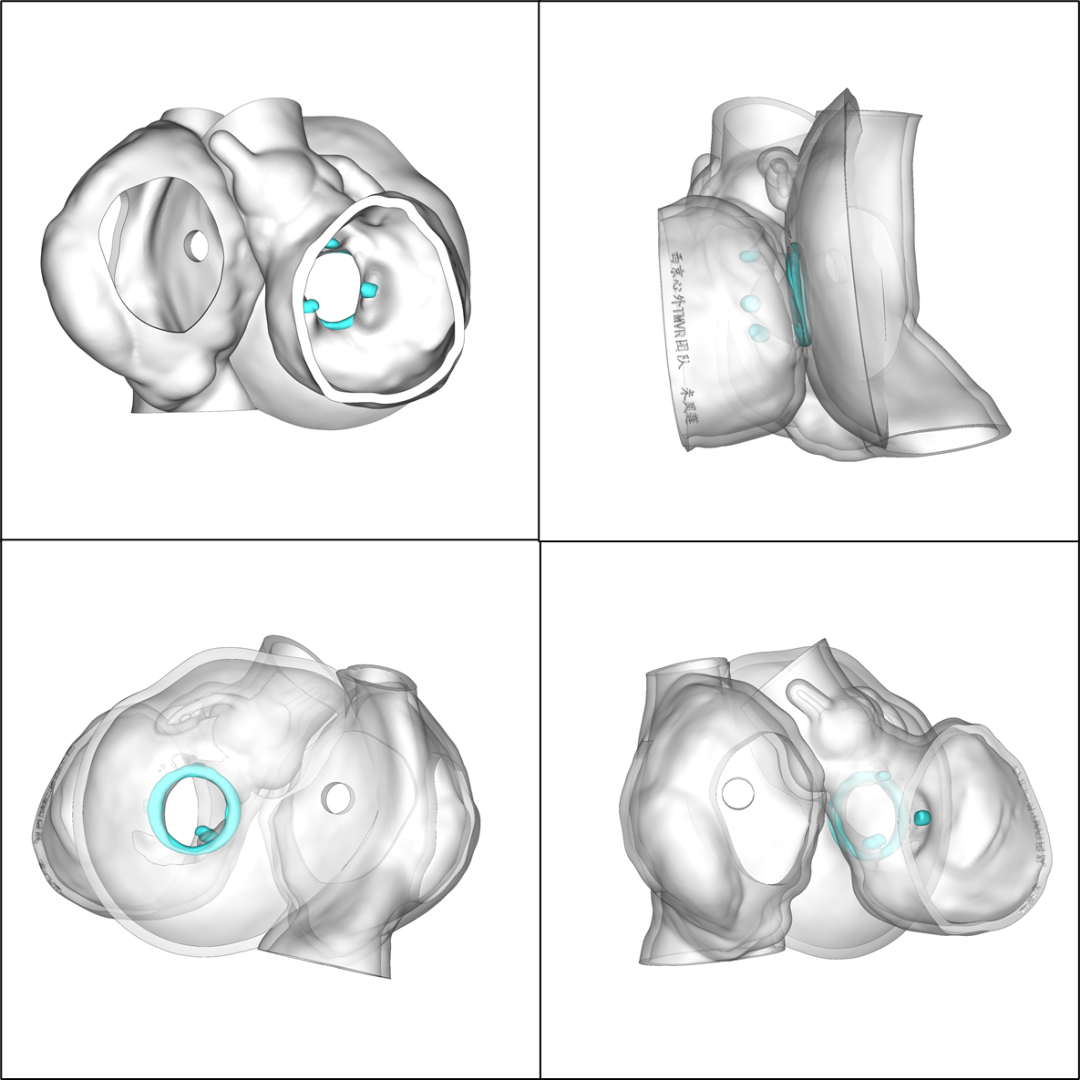

术前CT评估:

术前心脏3D模型:

本例手术,术前结合CT及3D打印技术周密规划手术策略,术中精准定位房间隔穿刺位置,结合预弯长鞘应用,有效提高了TMVR瓣中瓣手术安全性和手术效率,正所谓“化曲为直,捷径通优”。